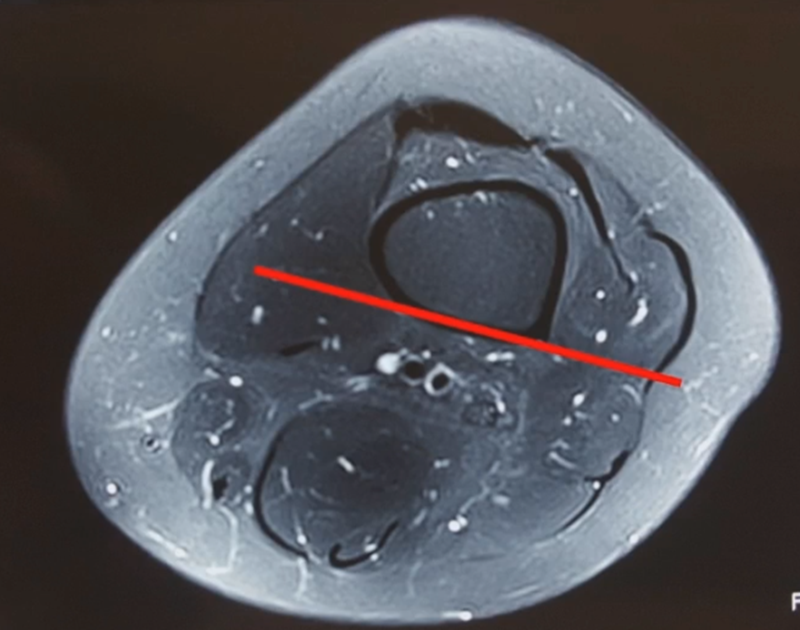

(2)术后力线丢失

对于力线丢失原则是重新矫正力线,重新固定,通常在合页端加上内固定物,主要目的是为了抗旋,有一些截骨端还需要进行植骨。术后早活动晚负重。

病例,X患者,女,双侧外翻膝,行双侧DFO。

术后6周摔伤,一侧出现膝内翻。

影像学检查显示左侧出现合页断裂。

进行翻修,术前力线显示内翻。

术中发现螺钉松动,截骨端出现坎插迹象。

近端螺钉松开,调整力线,重新固定后,在外侧加小钢板抗旋。

术后10周复查,力线较好。